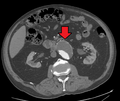

-

A ruptured AAA with an open arrow marking the aneurysm and the closed arrow marking the free blood in the abdomen

An axial contrast enhanced CT scan demonstrating an abdominal aortic aneurysm of 4.8 by 3.8 cm